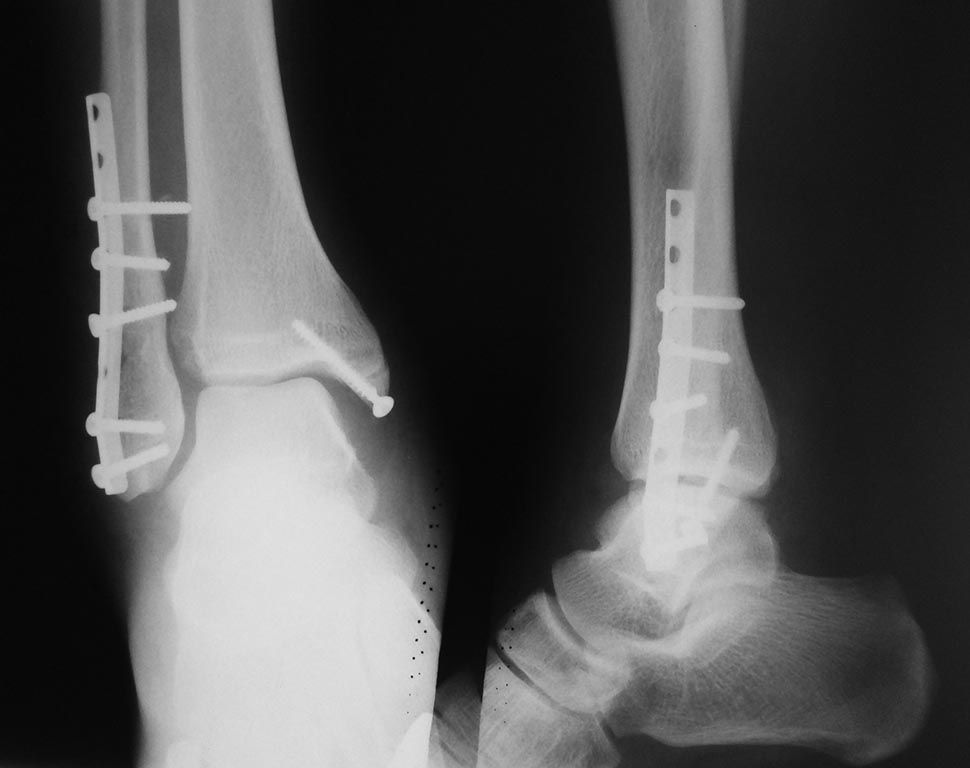

Рентгенограмма разрыва межберцового синдесмоза

Цена операционного лечения зависит от степени повреждения связок, сопутствующих патологий и переломов. Послеоперационное лечение на третьей стадии проводят, как указано выше в таблице.